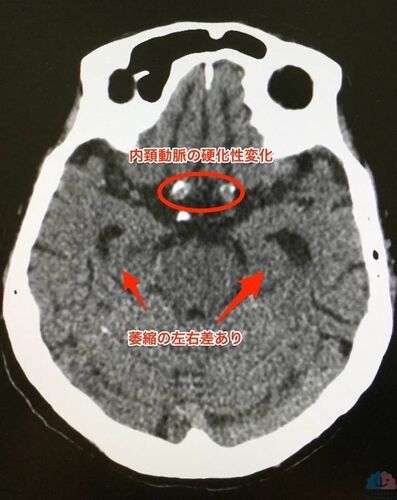

どちらも長谷川式テスト22点だが、対象的な87歳。

支える人が周囲にいるのかどうか。いるならば、その人達に何をお願いすべきか。いなければ、どのように支援体制を構築していけばよいのか。薬は必要なのか。必要でないならば、どのようにして病院とのつながりを保てばよいのか。薬が必要なら、その量や内服回数はどの…